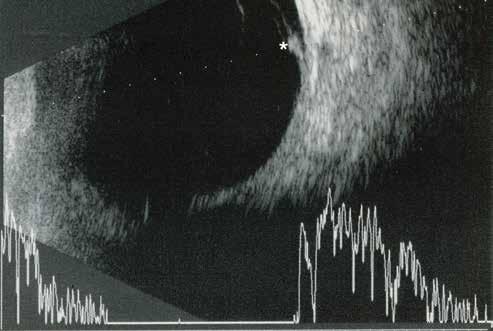

MNV may also develop in patients with central serous chorioretinopathy. In this condition, the pathogenesis of MNV is not yet fully understood. It is known that it can occur after laser photocoagulation or photodynamic therapy as a compensatory response to treatment; however, MNV may also develop in cases without history of laser treatment. In these cases, MNV may develop in a manner similar to AMD, where the rupture of Bruch’s membrane due to chronic RPE changes and long-standing serous pigment epithelium detachment allows for the growth of Type 1 neovascularization.33–36 (Figure 6)

Figure 6. Multimodal imaging of Type 1 macular neovascularization secondary to central serous chorioretinopathy. Fluorescein angiography (A and B) showing pinpoints of hyperfluorescence with leakage in the late phase. Indocyanine green angiography (C and D) displaying the central hyperfluorescent area and the adiacent area of choridal hyperpermeability. Fundus autofluorescence (E) revealing abnormalities of retinal pigment epithelium. The en face of optical coherence tomography angiography (F) showing the neovascular network and the B-scan displaying the shallow irregular retinal pigment epithelium elevation with subretinal fluid (G).